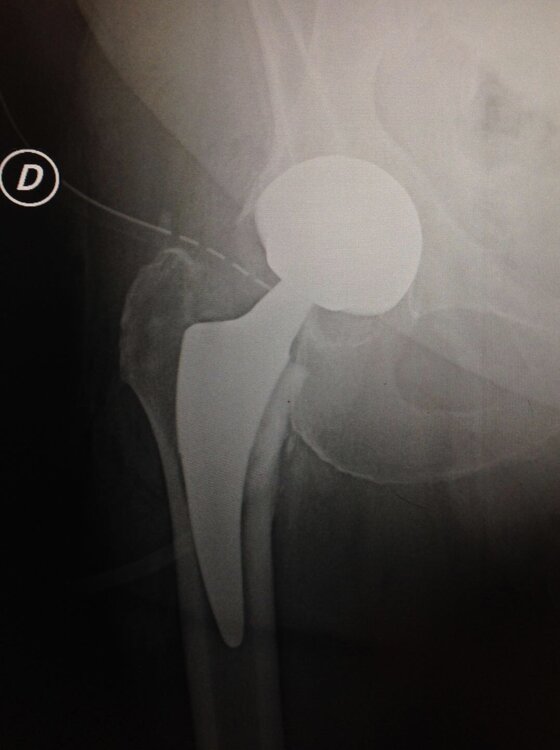

Nella coxartrosi severa e sintomatica la soluzione è l’intervento chirurgico di Artroprotesi di anca che ormai viene eseguito con accessi sempre più mini-invasivi e con risparmio di più osso possibile. Si utilizzano design protesici e materiali sempre più moderni e duraturi nel tempo. La deambulazione post-operatoria è immediata con ottimi risultati funzionali e soddisfazione da parte del paziente